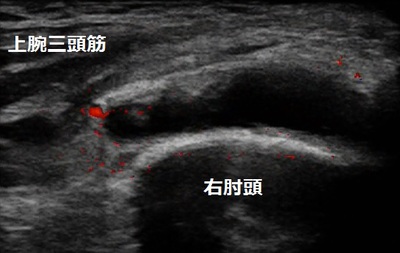

川越市 自営業男性。 右肘関節の痛み、右肘頭皮下包炎。

DIY作業で木材にカンナがけをしていたところ、カンナが木の節に引っかかり、右腕の曲げ伸ばしが

出来ないほど激痛が走りました。

翌日、病院を受診しレントゲン検査は異常なしで湿布と飲み薬を処方されました。 1週間、安静に

していましたが痛みは改善されませんでした。

当院来院時は右肘が瀰漫性に腫れて、熱感も有りました。超音波検査の結果、右肘頭の上部に水が

溜まっていることが認められました(画像、右肘頭上部の黒い部分)。

男性はテニスとソフトボール(投手)が趣味で、受傷前日にテニスとソフトボールの練習を1日中

行ったため、右腕がパンパンに張っていたという状況下でのDIY作業だったようです。